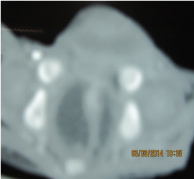

Investigations revealed anaemia, leucocytosis, deranged electrolytes and metabolic acidosis. USG was suggestive of a suspicious obturator hernia on right side. CT scan was suggestive of bulging of a large complex cystic structure with air-fluid level on the right side. Sagittal reformations also suggested the inferior descent of the cystic structure through the perineal floor (Figures 4 &5). The deranged laboratory parameters were corrected and the child was taken for emergency exploration. Intra-operatively, it was found that the massive hydrocolpos was protruding through the perineum as the bulge. There was no perineal or obturator defect. Drainage of the massive hydrocolpos was done by an abdominal vaginostomy (Figures 6&7).

Figure 5 Sagittal reformations also s/o the inferior descent of the cystic structure through the perineal floor.